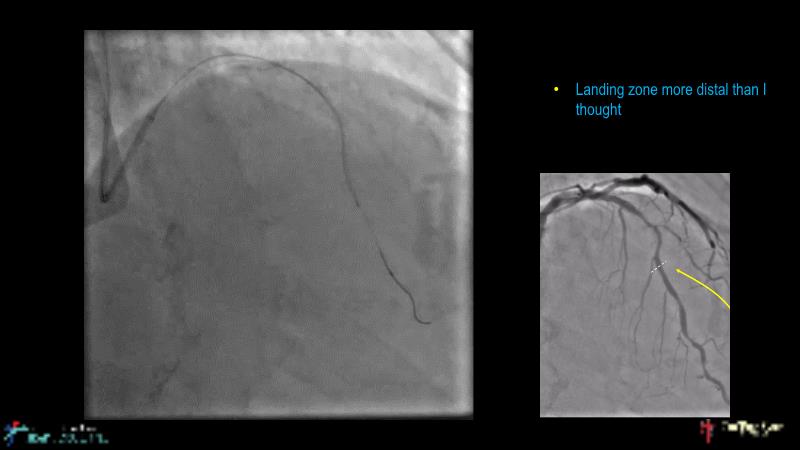

This session is recommended for you if you are seeking insights into the advantages of using IVUS imaging over visual assessment for better outcomes in left main bifurcation procedures. Discuss with experts the benefits of using RotaCUT in lesion preparation for left main bifurcation and explore the impact of high radial strength stents on the procedure's success.

• To understand why the use of IVUS imaging is different from seeing with experienced eyes to achieve improved left main bifurcation outcome